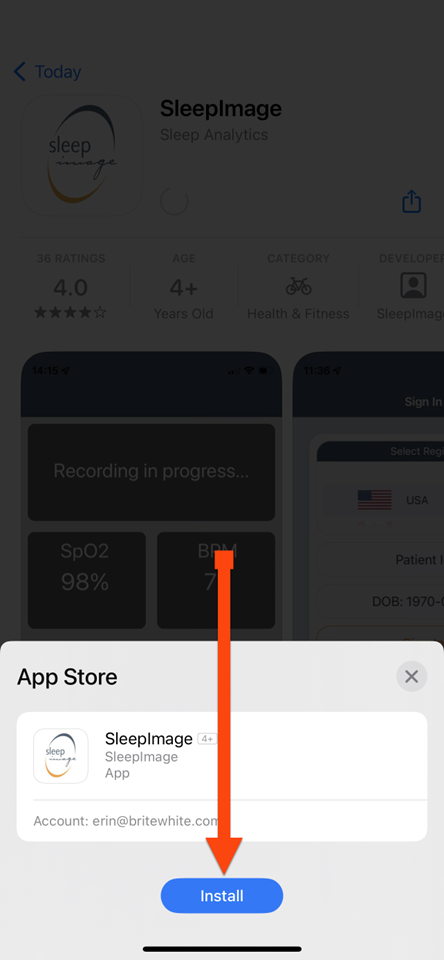

SLEEPIMAGE APP (iPhone)

SLEEPIMAGE APP (iPhone)

SLEEPIMAGE APP (iPhone)

SLEEPIMAGE APP (iPhone)

SLEEPIMAGE APP (iPhone)

SLEEPIMAGE APP (iPhone)

SLEEPIMAGE APP (iPhone)

SLEEPIMAGE APP (iPhone)

SLEEPIMAGE APP (iPhone)

SLEEPIMAGE APP (iPhone)

SLEEPIMAGE APP (iPhone)

SLEEPIMAGE APP (iPhone)

SLEEPIMAGE APP (iPhone)

SLEEPIMAGE APP (iPhone)

SLEEPIMAGE APP (iPhone)

SLEEPIMAGE APP (iPhone)

SLEEPIMAGE APP (iPhone)

SLEEPIMAGE APP (iPhone)

SLEEPIMAGE APP (iPhone)

SLEEPIMAGE APP (iPhone)

SLEEPIMAGE APP (iPhone)

SLEEPIMAGE APP (iPhone)

SLEEPIMAGE APP (iPhone)

SLEEPIMAGE APP (iPhone)

SLEEPIMAGE APP (iPhone)

SLEEPIMAGE APP (iPhone)